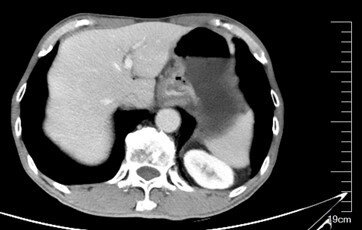

患者王先生,64歲。2021年6月出現(xiàn)饑餓后上腹部隱痛不適,同年9月查胃鏡見(jiàn)賁門潰瘍性病灶。病理示:(賁門)低分化腺癌。腹盆增強(qiáng)CT示胃底賁門壁占位,考慮胃癌,伴小彎側(cè)增大淋巴結(jié)?;颊呶纲S門處巨大潰瘍性腫瘤伴胃周淋巴結(jié)腫大,胃腸外科專家建議先行術(shù)前治療。近兩年,胃癌的治療有了很大的進(jìn)展?;贖er-2,PD-L1以及錯(cuò)配修復(fù)蛋白表達(dá)情況,個(gè)體化治療,延長(zhǎng)胃癌患者的生存。王先生胃部腫瘤組織進(jìn)一步做了免疫組化檢查,結(jié)果提示沒(méi)有錯(cuò)配修復(fù)蛋白缺失,PD-L1(+,CPS=3),HER-2(2+),F(xiàn)ISH檢測(cè)HER-2陽(yáng)性。根據(jù)患者免疫組化的結(jié)果,基于2021年胃癌研究的進(jìn)展,患者接受信迪利單抗+曲妥珠單抗+FLOT方案治療。2021年12月全麻下行腹腔鏡下全胃根治性切除術(shù)。術(shù)后病理見(jiàn)少許癌細(xì)胞殘留,(全胃)間質(zhì)纖維組織增生伴淋巴細(xì)胞、漿細(xì)胞浸潤(rùn)及組織細(xì)胞反應(yīng),局部見(jiàn)炎性肉芽組織形成,Becker分級(jí):1b級(jí)。標(biāo)本兩切緣、大網(wǎng)膜及另送食管切緣均未見(jiàn)癌組織累及,小彎淋巴結(jié)(25枚)、大彎淋巴結(jié)(4枚)、第16組淋巴結(jié)(4枚)呈反應(yīng)性增生,送檢第12A淋巴結(jié)為神經(jīng)組織。近來(lái)胃癌的免疫治療有了長(zhǎng)足發(fā)展。免疫聯(lián)合治療給胃癌患者帶來(lái)明顯生存獲益。尤其是在Her-2陽(yáng)性患者中,免疫聯(lián)合曲妥珠單抗聯(lián)合化療客觀有效率高,縮瘤效果明顯。本例Her-2陽(yáng)性局部晚期胃癌患者,通過(guò)免疫+曲妥珠單抗+化療取得了非常好的治療效果。一例外院診治的胃癌腹膜廣泛轉(zhuǎn)移伴大量腹水患者,沒(méi)檢測(cè)腫瘤組織的Her-2、PD-L1以及錯(cuò)配修復(fù)蛋白表達(dá),只用化療,腹水一直增加,咨詢我接下來(lái)如何治療?我告訴他一定要明確Her-2、PD-L1以及錯(cuò)配修復(fù)蛋白表達(dá)狀態(tài),基于這些指標(biāo),制定針對(duì)性的方案,才可能最大程度的從治療中獲益。蒲汪旸醫(yī)生蘇州大學(xué)附屬第二醫(yī)院,胃癌專病門診時(shí)間:每周四上午